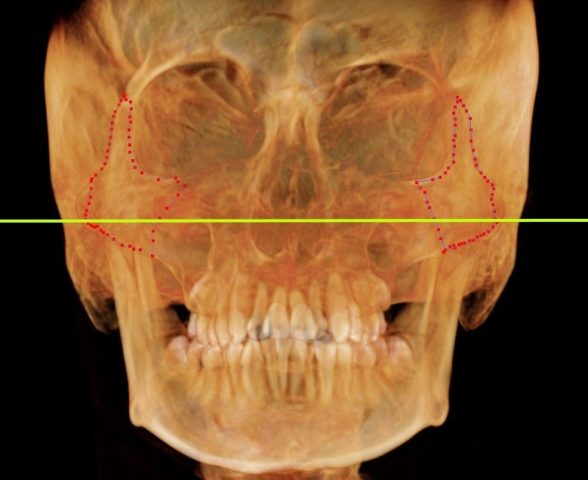

頬骨_痛い時_頬骨の高さの水平線

上のラインで、顔を輪切りにすると。

頬骨_痛い時_頬骨と上顎洞

CT像は、こうなります。